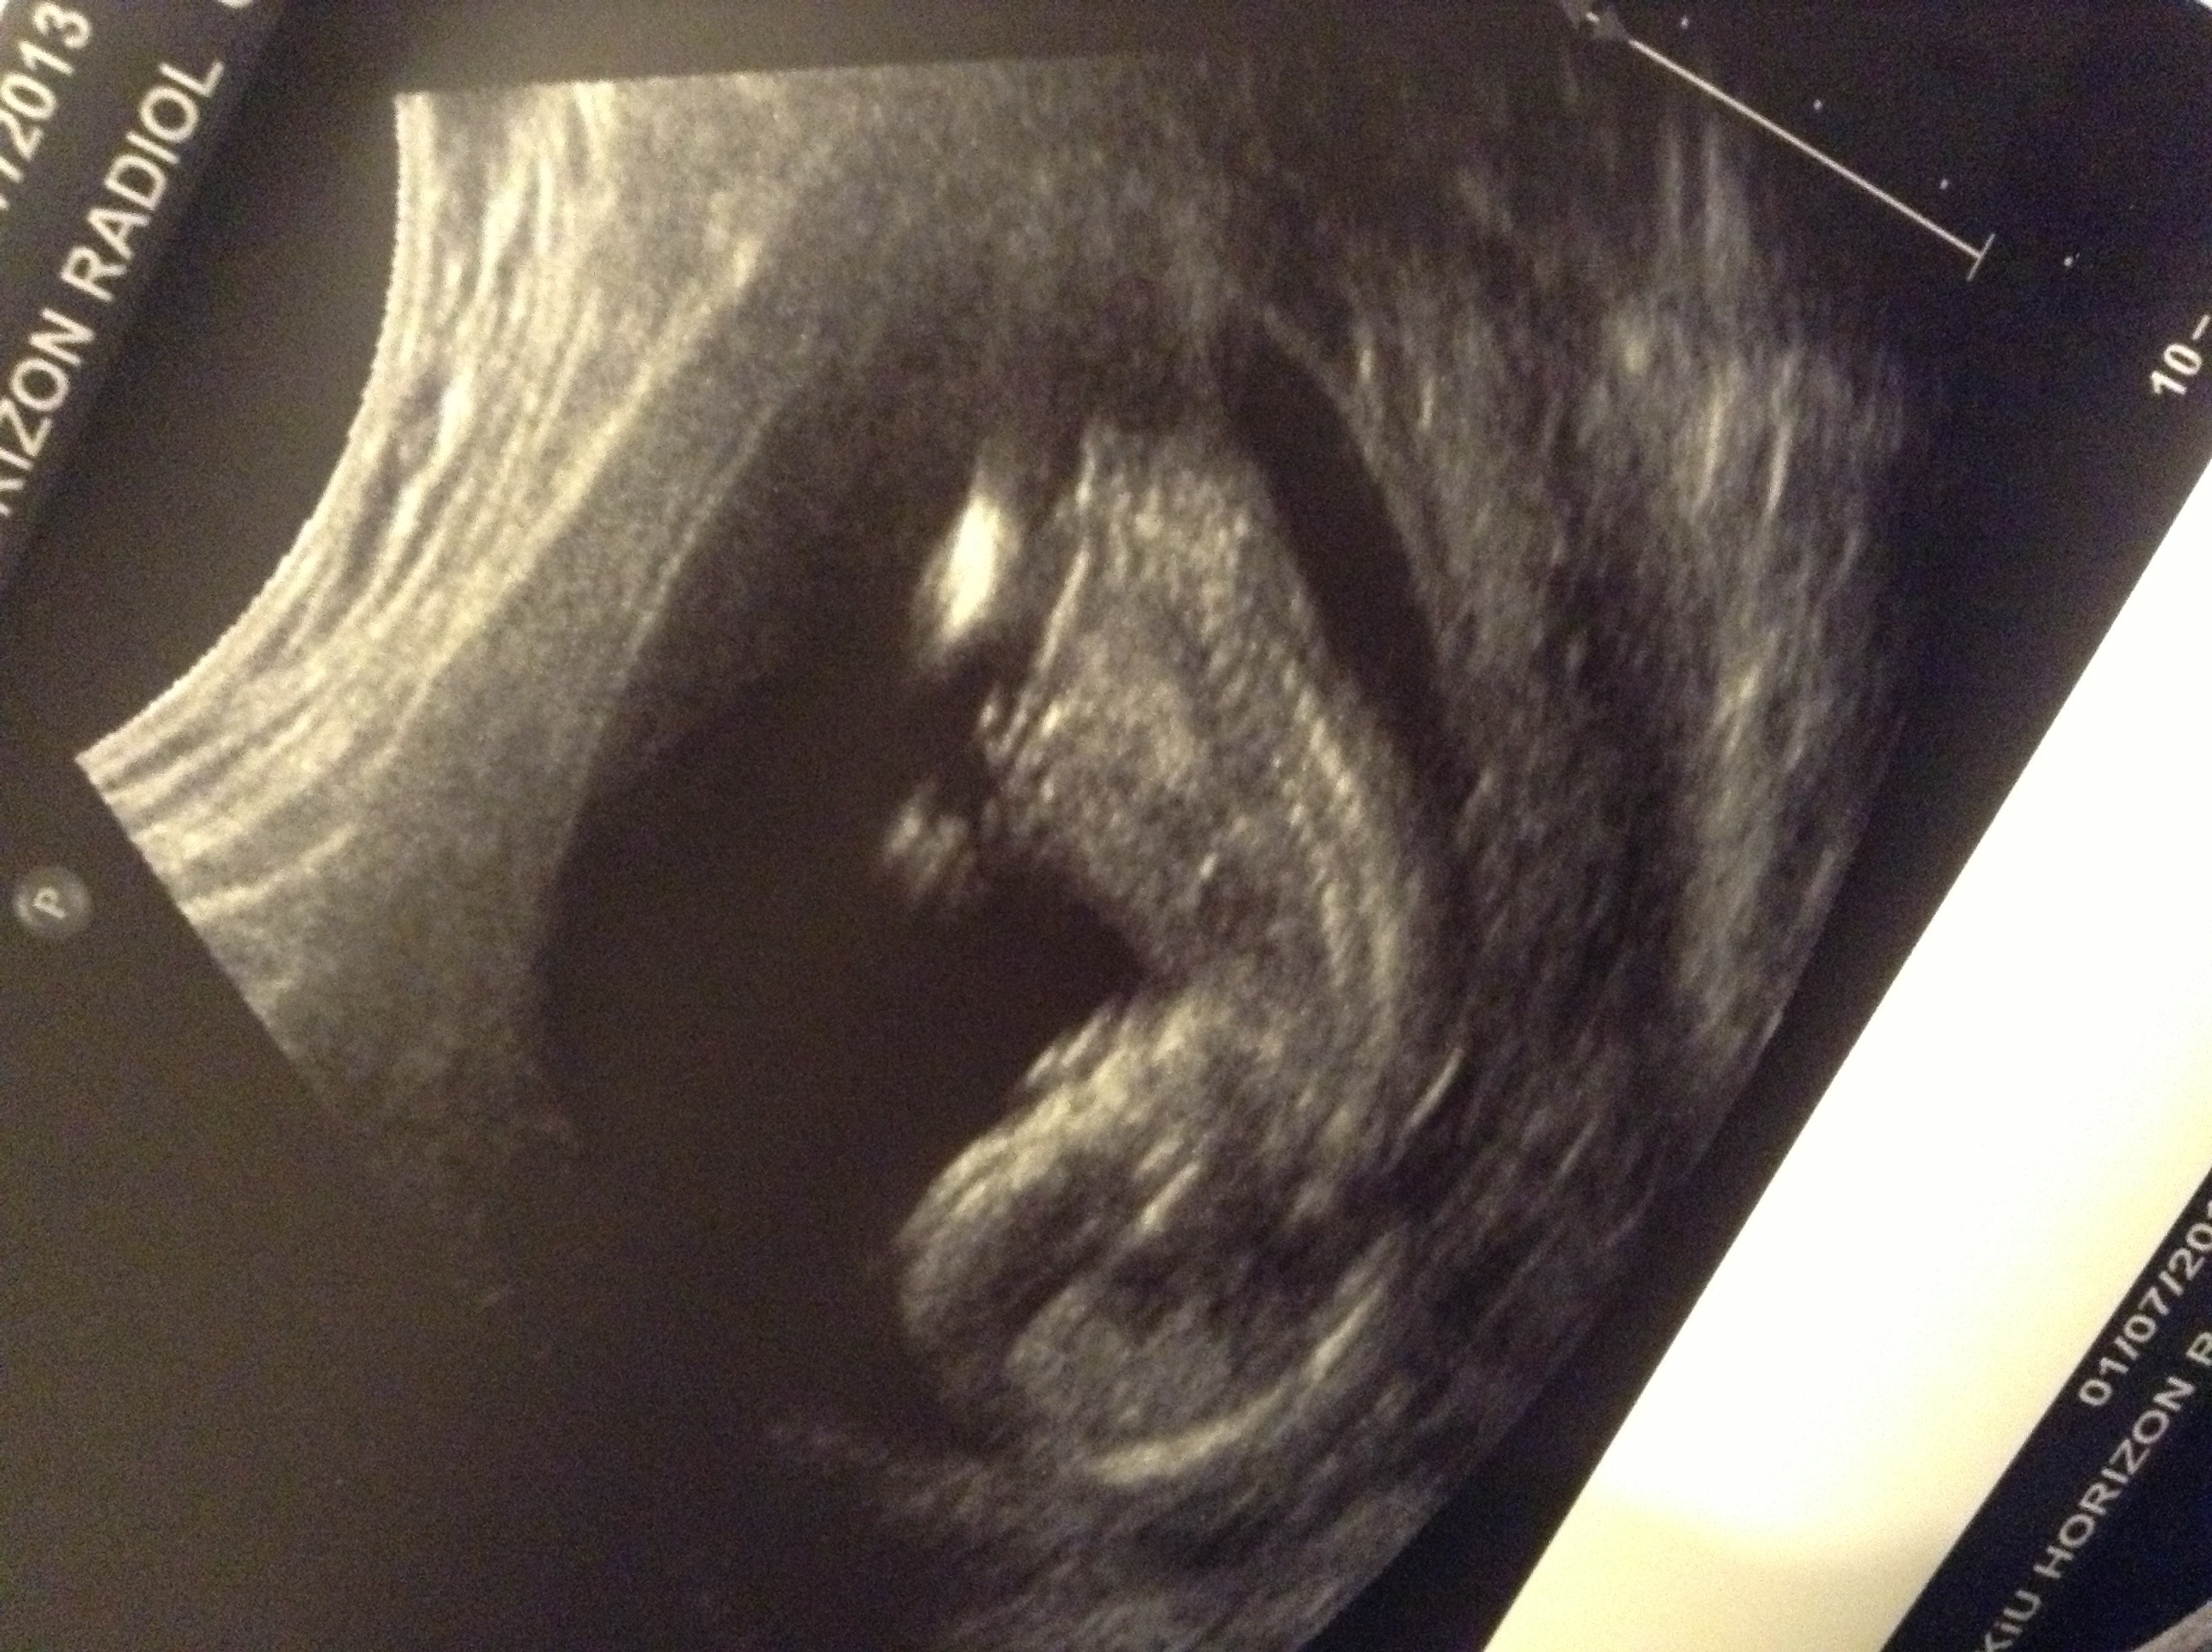

Had another scan due to spotting, placenta is over the cervix so thats prob whats causing it. Is that a nub behind leg?Attachment 12129

Funny angle I know but I think I can see a wee nub out by the bum